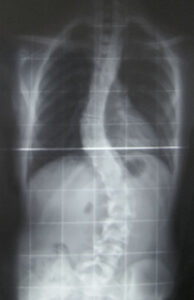

Studies (Here, HEREÂ and more HERE) show muscle atrophy (and development of fatty tissue within once healthy tissue) does not spontaneously resolve after surgery. The muscles have been found to look like a piece of poor quality fatty steak. You cannot allow that to happen.